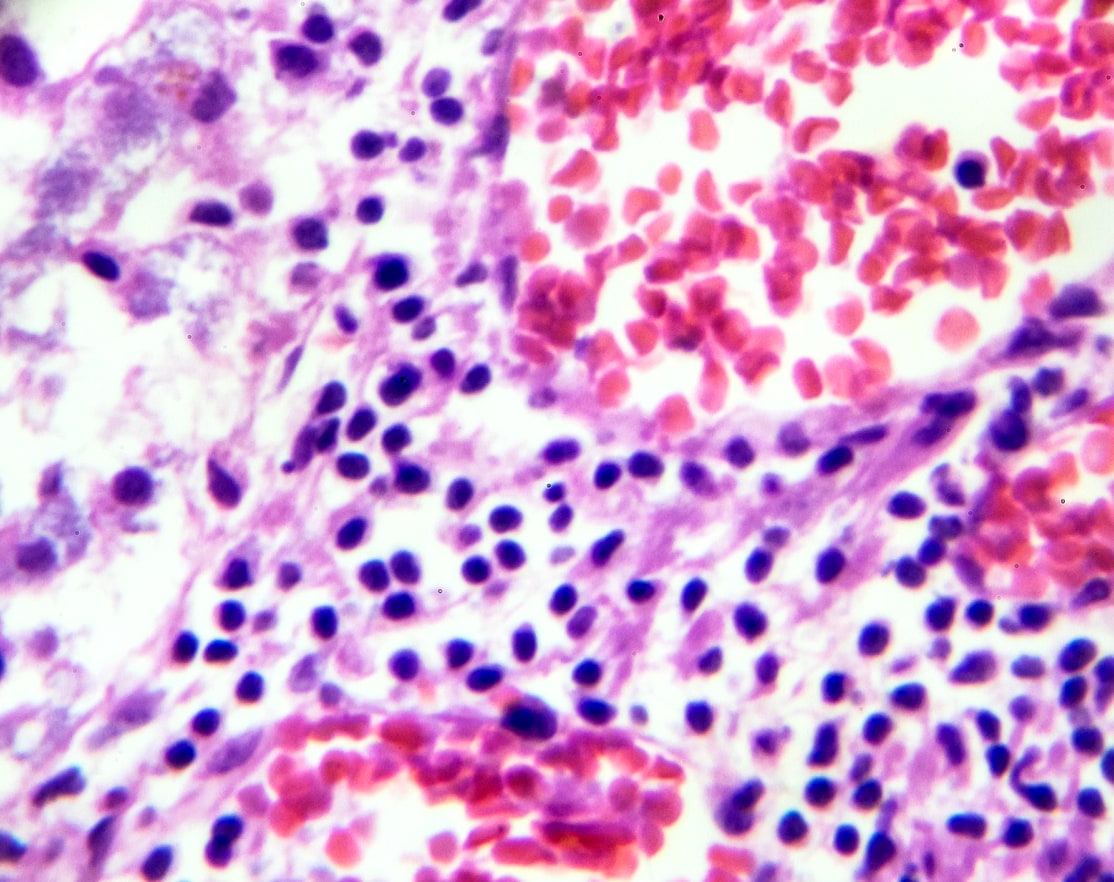

indolent Non-Hodgkin Lymphoma

Lipid rafts play a significant role in the pathophysiology of indolent non-Hodgkin lymphoma (iNHL), especially in regulating b-cell receptor (BCR) signaling, cell survival, and resistance to therapy. iNHL includes subtypes like follicular lymphoma (FL) and marginal zone lymphoma (MZL) and Waldenström macroglobulinemia (WM) which tend to have slow progression but are often difficult to cure. Lipid rafts in these lymphomas help orchestrate key signaling pathways essential for lymphoma cell proliferation and survival.